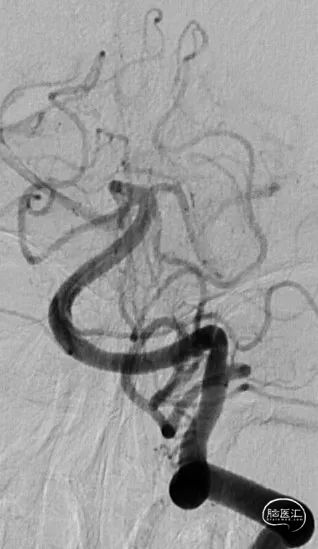

DSA结果:右侧颈内动脉后交通段动脉瘤, 7.2mm*6.7mm*5.7mm,瘤体上多个小子囊,载瘤动脉异常扭曲及不规则狭窄,直径约4.2mm。

术前DSA、DSA 3D

动脉瘤为绝对宽颈,弹簧圈无法成篮,先半释放4.5mm*30mm Neuroform Atlas支架覆盖部分瘤颈,但弹簧圈仍突出于载瘤动脉,完全释放支架。头端位于颈内动脉末段,尾端位于眼段,支架顺利释放,Mark点显影良好。

治疗后工作位减影造影显示动脉瘤致密栓塞,子囊未显影载瘤动脉血流通畅。